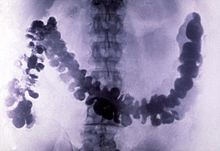

In 1908, barium sulfate was first applied as a radiocontrast agent in X-ray imaging of the digestive system.

Barium sulfate has a low toxicity and relatively high density of ca. 4.5 g·cm−3 (and thus opacity to X-rays). For this reason it is used as a radiocontrast agent in X-ray imaging of the digestive system (" barium meals" and " barium enemas"). Lithopone, a pigment that contains barium sulfate and zinc sulfide, is a permanent white that has good covering power, and does not darken when exposed to sulfides.